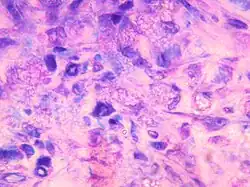

Coupe histologique de muscle de souris injecté avec une solution contenant des particules d'hydroxylapatite

Une coupe histologique est une tranche d'un organe suffisamment fine pour pouvoir être observée au microscope. Elles sont réalisées par un microtome pour des coupes de quelques µm d'épaisseur ou par un ultramicrotome pour des coupes d'environ 0,1 µm. Les tissus sont inclus dans des résines époxy ou dans de la paraffine.